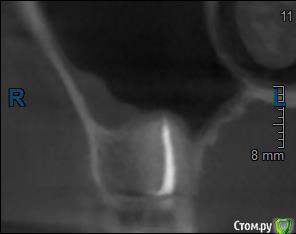

Здравствуйте! Верхний правый шестой зуб пломбировали 3 месяца назад. Примерно месяц назад он начал ныть, после насморка, сначала периодами, а теперь почти постоянно. При постукивание (ощущается не совсем так, как другие зубы) и пальпации десны он не болит. 2,5 месяца назад удаляли кисту из гайморовой пазухи. Может ли быть это какое-то воспаление и есть ли вероятность устранить его какими-нибудь антибиотиками, если да, то как, или может удалить зуб? Если есть воспаление, то какие могут быть последствия если не удалить зуб?

(Снимки с КТ, первые 8(Image) - сделаны сейчас,по 4 в разных проекциях, вторые 8(Before) - сделаны 5 месяцев назад до удаление кисты и повторного пломбирование зуба( до повторного пломбирование он реагировал на горячее, был запломбирован 3 года))

переличили зуб адекватно, во всяком случае по снимкам